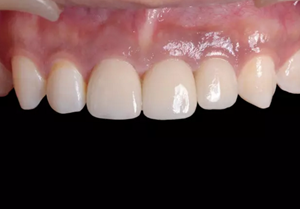

圖23 最終修復(fù)后即刻口內(nèi)像

圖25 最終修復(fù)后復(fù)查口內(nèi)像

(5)復(fù)查。種植體周圍骨水平穩(wěn)定,齦乳頭及齦高點位置穩(wěn)定,齦緣 曲線形態(tài)理想,唇側(cè)軟硬輪廓良好,功能滿意,修復(fù)效果符合預(yù)期。